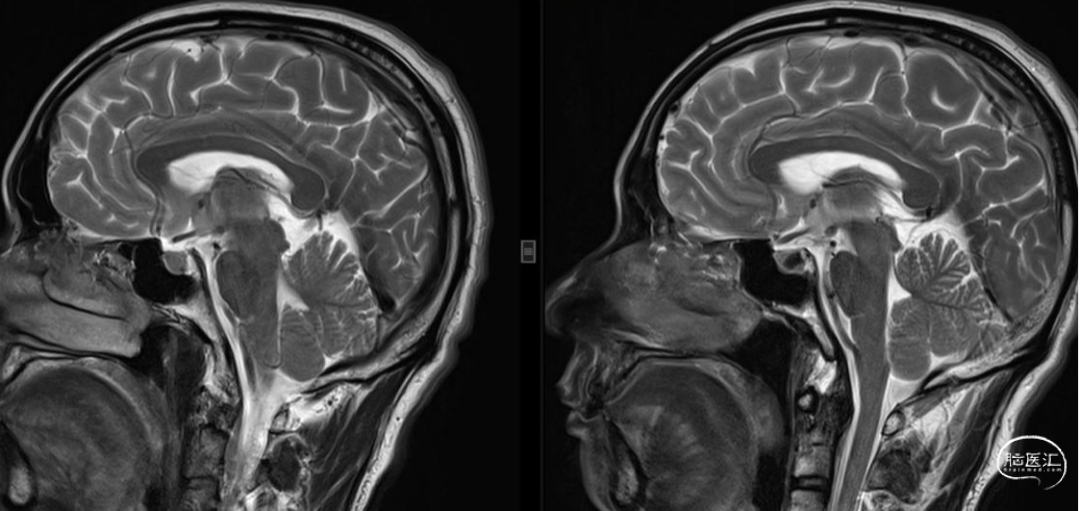

脑MRI检查可疑“脑下沉”征象,余无特殊。

椎管MRI检查发现为“高流量漏”,如上图。